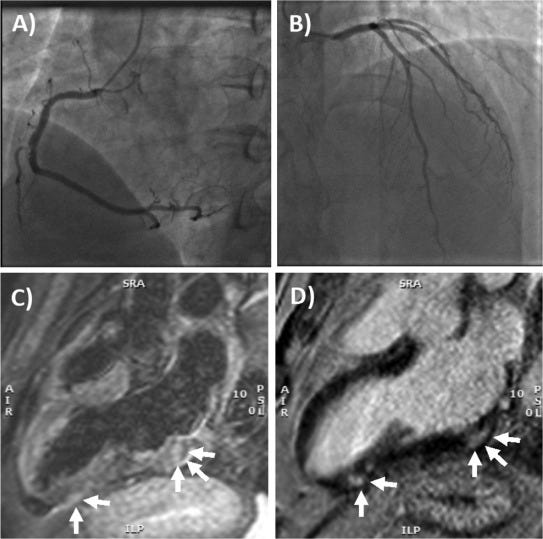

On arrival at the emergency department arterial blood pressure was 165/95 mmHg, heart rate 81 beats per minute, oxygen saturation 99% while breathing ambient air and body temperature 36.2 °C. Electrocardiogram (ECG) showed sinus rhythm, and minimal ST elevation on precordial leads, with peaked T waves. The chest x-ray was unremarkable (Supplemental Fig. 1A-B). Laboratory tests revealed elevated levels of biomarkers of myocardial necrosis, i.e. high-sensitivity (hs) troponin T 289 ng/L, and C-reactive protein 2.9 mg/L with normal blood cell counts, without evidence of peripheral eosinophilia (Table 1). Urgent coronary angiography carried out to rule out an acute coronary syndrome (Fig. 1A-B). Cardiac ventriculography showed preserved global left ventricular function. Chest pain resolved spontaneously within 4 h of admission. The patient was therefore transferred to the cardiology ward with a diagnosis of suspected acute myocarditis.

He underwent nasopharyngeal swabbing and the specimens were tested for common respiratory viruses by RT-PCR and resulted all negative. As expected, anti-SARS-COV-2 serology revealed a high-titer of IgG anti S1 and S2 proteins (titer > 400 AU/mL), and positive anti-nucleocapsid antibodies due to previous exposure. Hs-troponin T and CK-MB peaked on day 1 with values of 515 ng/L and 27 µg/L, respectively. No specific anti-inflammatory or steroidal therapy was administered, and CK-MB normalized at day 5 while hs-troponin T normalized within 7 days. Cardiac MRI showed non-dilated ventricles with preserved left (63%) and right ejection fraction (60%). There was focal subepicardial-intramyocardial (non-ischemic pattern) late gadolinium enhancement (LGE) involving the basal and apical segments of the infero-lateral wall, colocalized with signs suggestive for edema on T2 weighted images (Fig. 1C-1D), consistent with the diagnosis of acute myocarditis [7].’

‘Fig. 1. Coronary angiography and cardiac MRI. (A) The right coronary artery only had a mild plaque (<30% luminal diameter) in the mid portion, while (B) left main stem, left anterior descending artery and circumflex artery had no evidence of coronary plaques. (C) T2- weighted 3-chamber view on cardiac MRI, showing focal areas of edema involving the subepicardial-intramyocardial regions of the basal and apical segments of the infero-lateral wall (arrows). (D) Late gadolinium enhancement confirmed the presence of non-ischemic myocardial lesions in the basal and apical segments of the infero-lateral wall (arrows) consistent with acute myocarditis.’